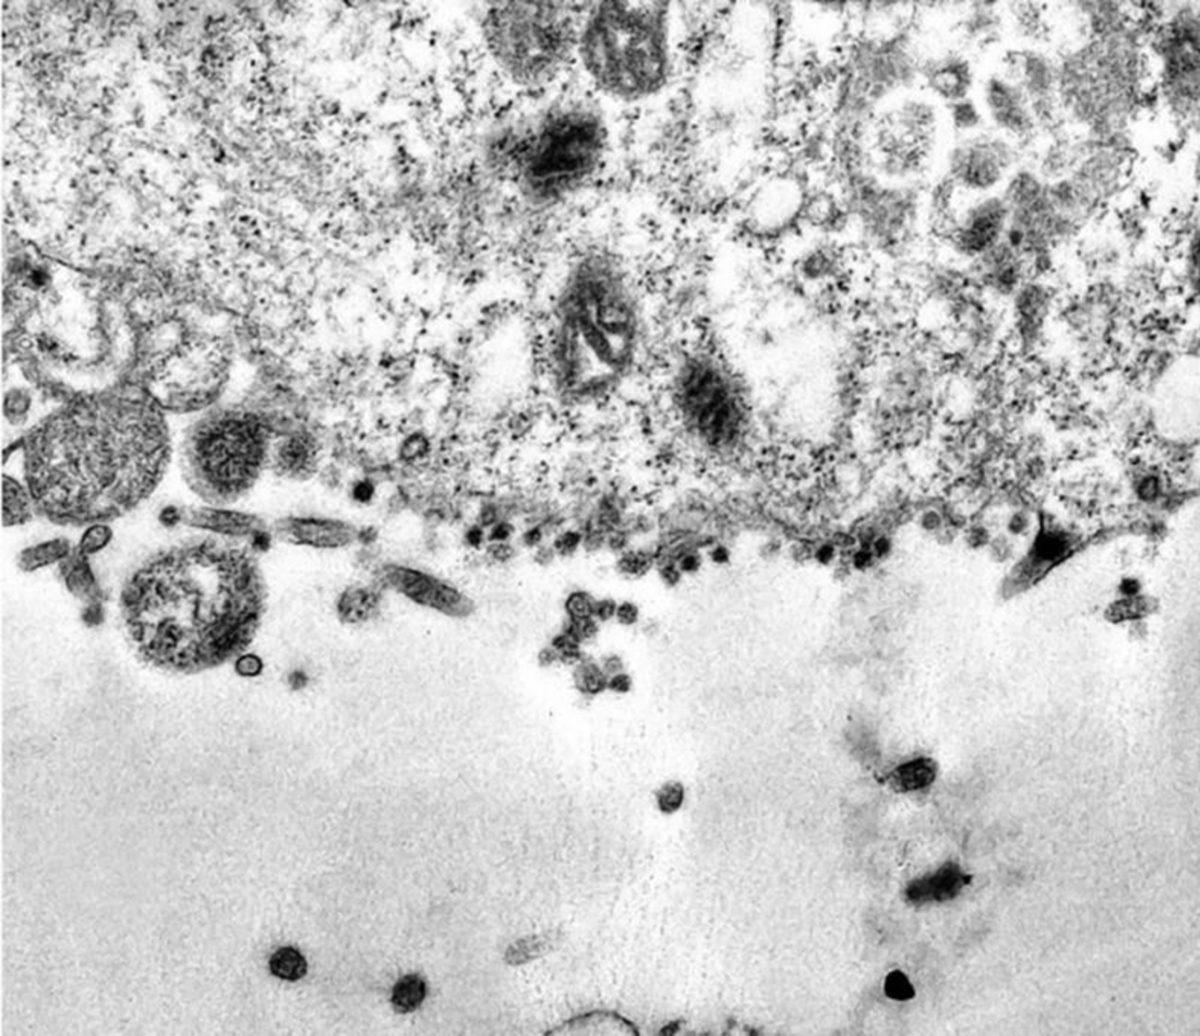

Koronavirüs incelemesine devam eden Brezilyalı bilim insanları, virüsün bir insan hücresini nasıl enfekte ettiğini gözlemleyebildiler. Bilim insanları, koronavirüsün hücreye saldırı anını görüntülemek için elektron mikroskobu kullandılar.

Koronavirüsün hücreye saldırdığı anların yer aldığı görüntülerde siyah noktalar olarak görülen koronavirüs, insan hücresinin genetikten sorumlu organeli olan sitoplazmaya saldırıyor. Sitoplazmaya saldıran virüs, bu şekilde insan hücresine enfekte oluyor.

Koronavirüsün hücreye saldırı anının görüntülerinde koronavirüsün ismini veren sivri protein uçları da görülüyor. Virüs bu sivri protein uçlarını kullanarak hücrelere tutunuyor. Koronavirüse karşı aşı çalışmalarında bu sivri protein uçlarının bağlandığı hücre proteinleri hedef alınıyor. Bu nedenle koronavirüsün hücreye nasıl girdiği ve sivri protein uçlarının nasıl çalıştığının belirlenmesi oldukça önemli.